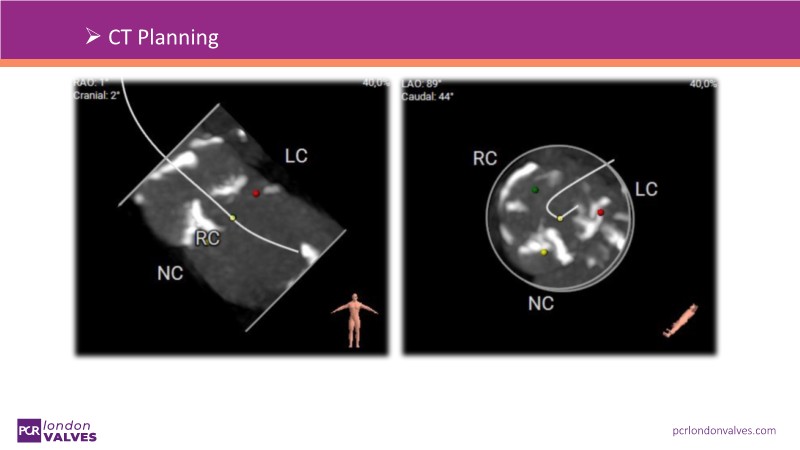

This session addresses emerging topics in structural heart disease by examining patient-centered solutions such as EVOQUE transcatheter tricuspid valve replacement (TTVR) and SAPIEN transcatheter heart valve-in-heart valve (THV-in-THV) procedures. It covers the latest data from Europe on redo TAVI, lifetime management strategies beginning with initial prosthesis planning, evolving patient selection for TTVR, and features an educational live case alongside expert panel discussions on procedure safety and efficacy.

- To understand the latest considerations and techniques for redo TAVI and get exposed to the latest data from Europe

- To learn how to maximise the benefits of TAVI with a lifetime management strategy that starts with the planning of the first prosthesis